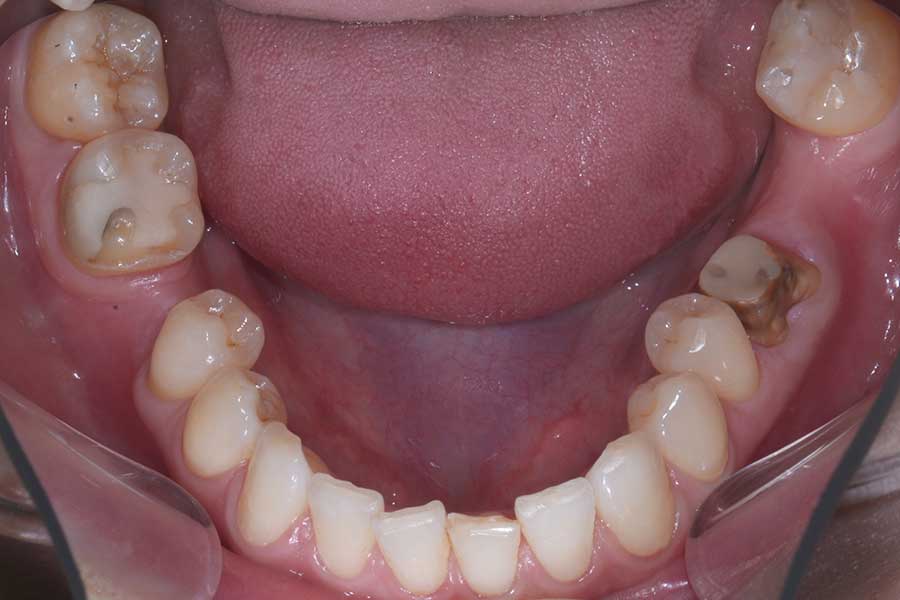

治療前

主訴 インプラント治療前にブラックトライアングルを消したい

治療内容 上下顎ラビアル矯正(表側矯正)